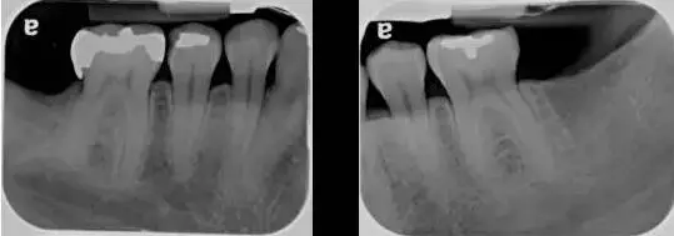

1、除了临床检查,X 光片也是必不可少的。在牙周检查里,最常用的是根尖片和咬翼片,有时候再加上全景片。

2、在读根尖片前,首先要确定 X 光片的拍摄质量,换句话说,这张根尖片有没有用于诊断的价值。

3、垂直咬翼片更适合牙周检查。因为牙周病患者通常有骨吸收,如果吸收严重,水平咬翼片可能没法显示牙槽嵴,而这时垂直咬翼片就显示了其优点。